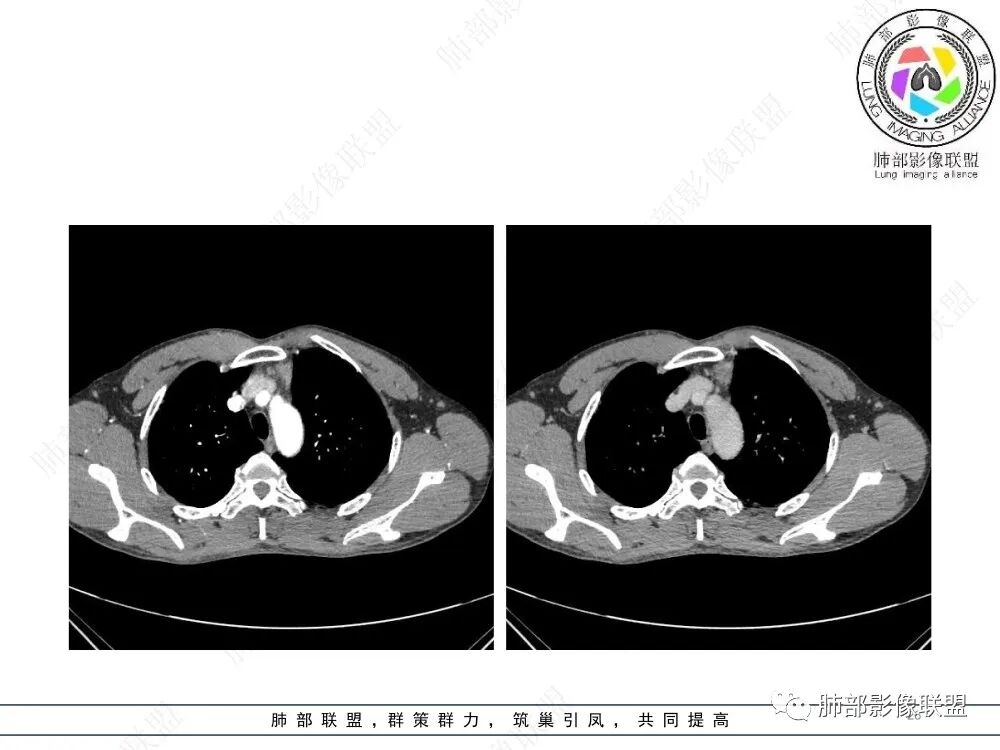

衡妈🇨🇳:中年男性,前纵隔偏左侧实性占位,密度相对均匀,边缘分叶,周围脂肪结构略模糊,增强后动脉期不均匀强化,有低密度区,纤维分隔显示不清。考虑胸腺瘤B1 B2型。

流心明智:男,47,咳嗽、咳痰1年余。胸部CT:前纵膈偏左类圆形肿块,瘤肺界面清晰光整,纵隔侧部分层面絮状影?平扫密度较均匀,增强后轻度强化,内可见宽带及线样低密度分隔。邻近左上肺受压凹陷。考虑胸腺肿瘤,AB型?胸腺Ca?鉴别淋巴瘤、N源性肿瘤、CD等。

在路上:考虑胸腺瘤,密度均匀,无钙化,轻度强化,边缘请放射线:前纵膈偏左侧肿块,边缘光滑清晰,周围脂肪间隙清晰,渐进性强化,密度不均,考虑胸腺瘤,鉴别淋巴瘤。

2、影像特点:前纵隔偏左侧软组织影,密度相对均匀,未见明显包膜钙化及实质内钙化,局部边缘浅分叶,周围脂肪间隙密度增高、浑浊,未见侵犯大血管、未见纵隔内淋巴结转移、未见侵犯心包内结构、未见胸膜转移结节、未见肿块沿着纵隔胸膜蔓延,未见胸腔积液。增强后动脉期不均匀强化,未见明显纤维分隔。